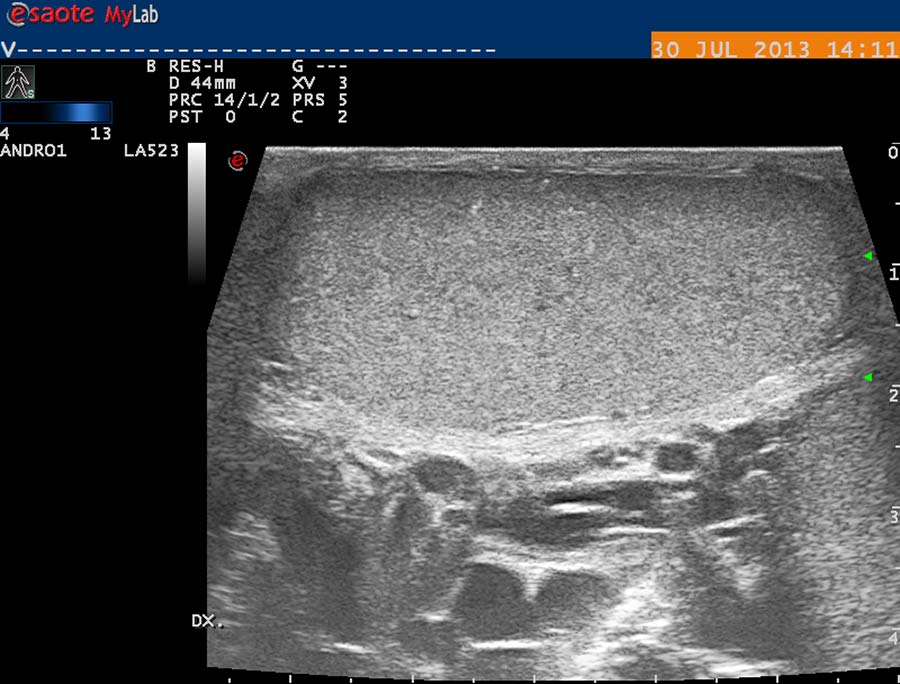

USG diagnostika vyžaduje odpovídající vybavení (obr. 12), zkušenosti a dostatek času. Vyšetření USG provádíme po termografickém vyšetření, na lůžku vyhřívaném na 30 st. Celsia, ultrasonografický gel zahříváme ve vodní lázni na teplotu 35 stupňů. Chladová kontrakce musculus cremaster vede k falešně negativním nálezům. Základní projekcí je koronární sken varlete (obr. 14) následovaný volumometrií ve dvou rovinách (obr. 15). Již na těchto skenech varlete je patrné rozšíření intratestikulárních cév, lépe je však viditelné při harmonickém („tissue enhancement imaging – TEI“) zobrazení (obr. 16, 17), a při barevném Dopplerovském zobrazení (Power Doppler) s TEI (obr. 18) s měřením šíře stěny a lumen žíly. Objemné dilatované žíly pampiniformního plexu jsou velmi dobře patrné na kolorizovaném TEI zobrazení (obr. 19), kde je možné zachytit pohyb venózní krve v souvislosti s dechem, intraabdominálním (IAP) a intrathorakálním tlakem. Informaci o atrofizaci tkáně získáme ze záznamu deformace kontury tunica albuginea podložkou, kterou je měkká buničina vložená pod skrotum (obr. 20, obr. 21 s volumometrií). Triplexní Dopplerovský záznam umožní hodnotit délku žilního refluxu a rychlost proudu refluktující krve v inspiriu, reflux při zvýšení intraabdominálního tlaku (obr. 22,23). Duplexní Dopplerovský záznam při harmonickém zobrazení s kolorizací zachycuje senzitivně změnu rychlosti proudění při refluxu v inspiriu s navazujícím zvýšením rychlosti při IAP (obr 25). Významná je možnost zachycení refluxu při klidném dýchání (respirační reflux, obr. 26).

obr. 14